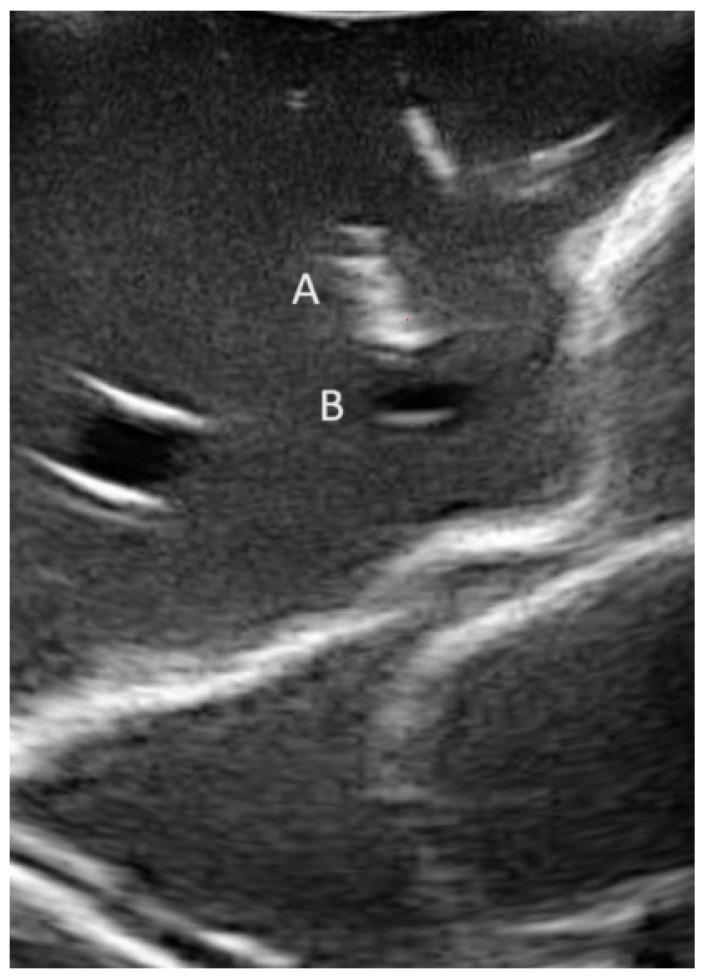

Mixed reality (MxR) enables the projection of virtual three-dimensional objects into the user's field of view via a head-mounted display (HMD). This phantom model study investigated three different workflows for navigated common femoral arterial (CFA) access and compared it to a conventional sonography-guided technique as a control. A total of 160 punctures were performed by 10 operators (5 experts and 5 non-experts). A successful CFA puncture was defined as puncture at the mid-level of the femoral head with the needle tip at the central lumen line in a 0° coronary insertion angle and a 45° sagittal insertion angle. Positional errors were quantified using cone-beam computed tomography following each attempt. Mixed effect modeling revealed that the distance from the needle entry site to the mid-level of the femoral head is significantly shorter for navigated techniques than for the control group. This highlights that three-dimensional visualization could increase the safety of CFA access. However, the navigated workflows are infrastructurally complex with limited usability and are associated with relevant cost. While navigated techniques appear as a potentially beneficial adjunct for safe CFA access, future developments should aim to reduce workflow complexity, avoid optical tracking systems, and offer more pragmatic methods of registration and instrument tracking.

混合现实(MxR)能够通过头戴式显示器(HMD)将虚拟三维物体投射到用户的视野中。这项体模模型研究调查了三种不同的导航股总动脉(CFA)穿刺工作流程,并将其与传统超声引导技术作为对照进行比较。10名操作者(5名专家和5名非专家)共进行了160次穿刺。成功的CFA穿刺定义为在股骨头中间水平穿刺,针尖位于中心腔线,冠状面插入角度为0°,矢状面插入角度为45°。每次尝试后使用锥形束计算机断层扫描对位置误差进行量化。混合效应模型显示,与对照组相比,导航技术从进针点到股骨头中间水平的距离明显更短。这突出表明三维可视化可以提高CFA穿刺的安全性。然而,导航工作流程在基础设施方面较为复杂,可用性有限,且成本较高。虽然导航技术似乎是安全CFA穿刺的潜在有益辅助手段,但未来的发展应旨在降低工作流程的复杂性,避免光学跟踪系统,并提供更实用的配准和器械跟踪方法。